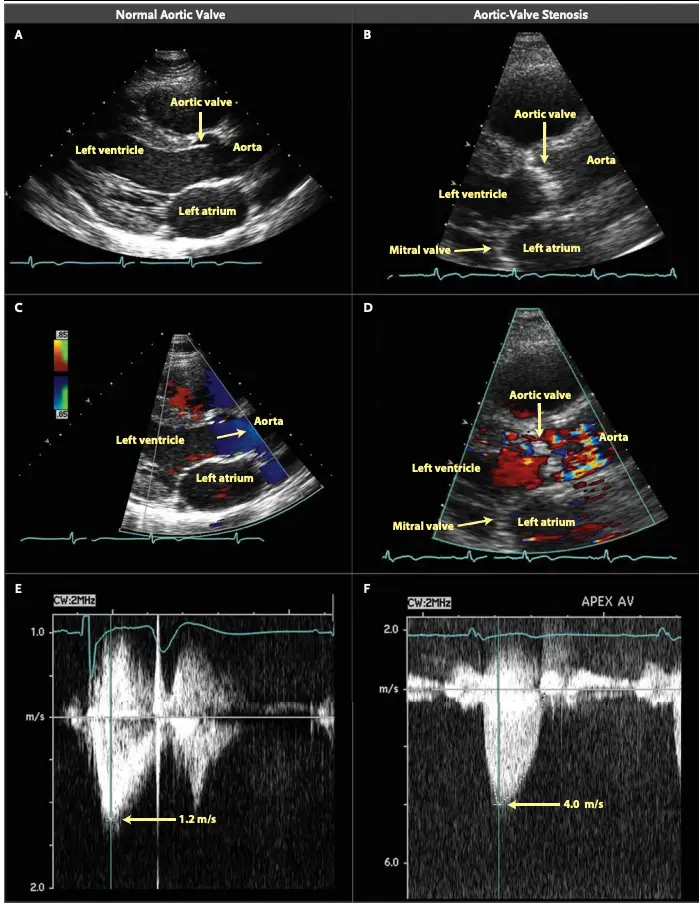

When the valve is tight, the velocity of the blood going through the valve must increase to keep the flow through the LVOT and the aortic valve constant. Recall, , so the velocity has to ↑ when the area is ↓ to maintain the flow rate. Analogy: Think of crimping the water hose while you’re watering your plants. We use the modified Bernoulli equation () to convert the Doppler velocity to pressure gradients across the AV. So as the blood shoots through that tight aortic valve and we clock a velocity of 4 m/s using Doppler on echo, we can convert that to a peak gradient of 64 mmHg, which raises our concern that that poor ventricle is working way too hard.

AVA < 1.0 cm2 Peak velocity > 4 m/s Mean gradient > 40 mmHg Peak gradient > 64 mmHg

- ==Valvular AS will be considered severe if mean gradient > 40 mmHg or peak velocity > 4 m/s (regardless of AVA)==

- Aortic velocity is measured using continuous-wave doppler ultrasound with examination from multiple acoustic windows

- Mean gradient is calculated by averaging instantaneous gradients over the systolic ejection period using the modified Bernoulli equation,

| Peak velocity (m/s) | <2.0 m/s | 2.0-2.9 | 3.0-3.9 | ≥4.0 | ≥5.0 |

Underestimation due to improper Doppler alignment across the Aortic Valve

If not parallel to the AS jet, you will not get the highest mean AV gradient or peak velocity across the AV → underestimate severity of AS. Importantly, you cannot overestimate the gradient (Exceptions: significant anemia or Subaortic Stenosis).